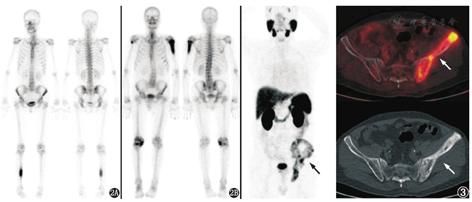

患者男,76岁。2018年外院前列腺穿刺活组织检查(简称活检)诊为前列腺癌[Gleason评分4+4,血清前列腺特异抗原(prostate specific antigen, PSA)>20 μg/L],予戈舍瑞林+比卡鲁胺治疗半年,PSA下降满意。1年后发现右足跟肿物,CT提示右足跟骨内6.1 cm×4.8 cm大小占位,外院全身骨显像示多发骨骼摄取增高灶,考虑为前列腺癌转移灶可能;盆腔MRI提示前列腺外周带右侧异常信号,右侧腹股沟及左盆腔淋巴结肿大;血清PSA 0.5 μg/L。鉴于18F-脱氧葡萄糖(fluorodeoxyglucose, FDG)PET/CT对前列腺癌的诊断效果欠佳,很大比例的前列腺癌及其转移灶为假阴性,诊断灵敏度仅为30%~50%[1];另外由于18F-FDG对于肿瘤的非特异性,其在判断前列腺局灶性炎性反应和前列腺癌中的特异性较差,仅有约20%的前列腺18F-FDG摄取增高灶被证实为前列腺癌[2],因此患者行68Ga-前列腺特异膜抗原(prostrate specific membrane antigen, PSMA)PET/CT(图1)以评估前列腺癌的情况。

PSMA是具有750个氨基酸的跨膜糖蛋白,在大多数前列腺癌的原发灶和转移灶中均高表达,且在低分化、转移或去势抵抗性前列腺癌中的表达明显增加,其表达水平是疾病预后的重要预测因素[3,4]。68Ga-PSMA PET/CT是以PSMA为基础的前列腺癌分子影像新技术,适应证主要包括前列腺癌靶向定位活检、手术与外放疗前分期、生化复发的前列腺癌病灶定位诊断、指导转移性去势抵抗性前列腺癌PSMA放射配体治疗、转移性前列腺癌全身治疗监测等。本例68Ga-PSMA PET/CT显像见前列腺增大,最大横截面6.1 cm×4.8 cm,前列腺腺体摄取不均匀增高,最大标准摄取值(maximum standardized uptake value, SUVmax)8.5,符合前列腺癌原发病灶的表现;盆腔及腹股沟淋巴结未见异常摄取。此外,四肢骨骼发现多处68Ga-PSMA摄取异常增高灶,包括右侧尺骨鹰嘴、左肱骨内侧髁、右股骨内侧髁、右侧髌骨、左胫骨上段、左腓骨下段、双侧跟骨,其中以右侧跟骨病灶最为显著,SUVmax 6.0,上述骨病灶均为单纯的溶骨性改变,较大的病灶呈膨胀性生长并破坏骨皮质。

肿瘤骨转移首先发生在红骨髓最丰富的中轴骨,这可能与血运和骨髓微环境有关。少见情况下,肿瘤骨转移也可能只出现于四肢骨骼而中轴骨不受累(图2)。但大部分的肿瘤骨转移以累及中轴骨为主,仅累及四肢远端骨骼且病灶多发的情况少见。前列腺癌骨转移通常为成骨性,以新骨形成为特征,这可能与前列腺癌释放的PSA可裂解甲状旁腺激素相关蛋白有关,其可阻断肿瘤诱导的骨质吸收,同时PSA也可激活骨微环境释放的成骨细胞生长因子。绝大部分的前列腺癌骨转移为成骨性,但其中也可有由破骨细胞介导的溶骨性成分,文献中也有一些个例报道表现为广泛溶骨性破坏的前列腺癌骨转移[6,7],但均很少见。本例有5个以上骨骼病灶,均分布于四肢长骨远端,所有病灶均为单纯溶骨性改变而未见成骨成分,这些特点提示要鉴别其他非前列腺来源的疾病,如原发性骨肿瘤或其他累及骨骼的系统性疾病。

68Ga-PSMA是诊断和评估前列腺癌的方法,但PSMA不仅仅表达于前列腺癌上皮细胞膜,其他实体肿瘤(如肺癌、肾癌、结肠癌、食管癌、甲状腺癌、脑肿瘤等)的新生血管内皮细胞也有PSMA的表达,这些肿瘤原发灶及转移灶能摄取68Ga-PSMA。此外,一些良性病变(如支气管扩张伴感染、结节病、Paget病等)也可能摄取68Ga-PSMA[8,9]。图3为1例前列腺增生合并骨盆Paget病的患者,血清PSA 13.51 μg/L,外院前列腺MR见前列腺外周带小片状异常信号,骨显像曾考虑前列腺癌骨盆转移,68Ga-PSMA PET/CT显像见左侧骨盆摄取不均匀异常增高,前列腺摄取未见异常,结合CT表现考虑骨盆Paget病。

本例因骨骼病变异于前列腺癌骨转移的表现,追问患者病史13年前曾行鼻腔孤立性浆细胞瘤手术及放疗,之后未见复发。结合病史及骨病特点,考虑多发性骨髓瘤可能,这恰好是典型的以单纯溶骨性骨病变为特点的骨病。之后患者行CT引导下右跟骨病灶穿刺活检,病理示纤维组织内见弥漫成片浆样细胞浸润,考虑多发性骨髓瘤;同时查血清蛋白电泳及免疫固定电泳示免疫球蛋白(immunoglobulin, Ig)G-λ型M蛋白阳性,证实了多发性骨髓瘤的诊断。